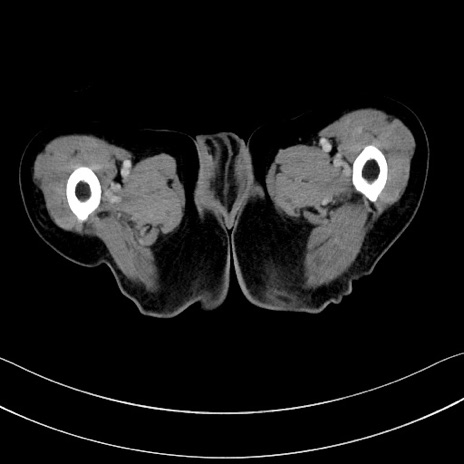

症例28(横断像)

【症例】60歳代男性

【主訴】嘔吐

【現病歴】胃癌にて胃全摘後。食思不振が悪化し、夜中に嘔吐することがある。

【既往歴】胃癌、胃全摘、脾摘、胆摘後

【データ】WBC 5900、CRP 10.56